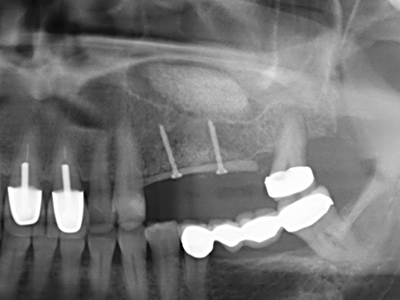

As shown in the past, basically any bone surgery procedure represents a possible indication for piezo surgery. Thus preparation of the mobile segment in distraction osteogenesis (Fig. 23-25) and sandwich osteotomy uses special attachments without endangering the blood supply to the crestal section, which is essential for the success of both techniques (Gonzalez-Garcia, Diniz-Freitas et al. 2008).

For removal of an implant, a vestibular bone cover that is replaced after removal of the implant screw can be prepared to retain the contour of the alveolar ridge.

There are additional applications in sinus surgery. Pathologies and foreign bodies can be removed from the sinus after concentric preparation of a generally trapezoid bone cover in the facial sinus wall. The bone cover is repositioned on conclusion of the intra-antral operation component and secured by wedging or adaptive sutures to prevent dislocation.

Purely orthodontic indications include orthognathic surgery, genioplasty (Fig. 27-30) and orbital decompression in patients with advanced endocrine orbitopathy as a result of Basedow’s disease (Ponto, Zwiener et al. 2014). Piezo devices are also used in maxillofacial surgery and to remove tumours at the base of the skull in various hospitals.